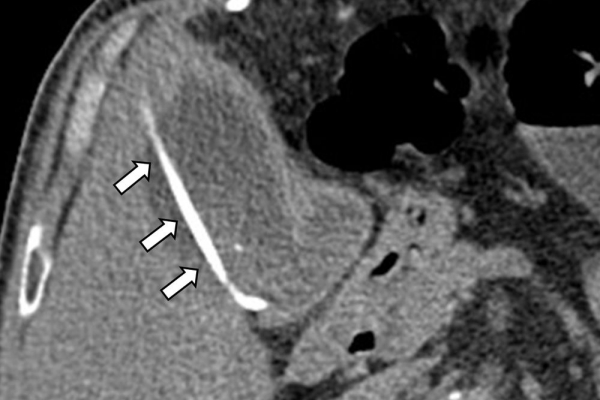

Η παροχέτευση των χοληφόρων σε αυτές τις περιπτώσεις θα πρέπει να γίνεται άμεσα, είτε ταυτόχρονα προς τα έξω και προς το 12κτυλο (έσω-έξω παροχέτευση), είτε μόνο προς τα έξω με τη βοήθεια pigtailκαθετήρα (εξωτερική παροχέτευση)

Η προσπέλαση σε όλες τις περιπτώσεις γίνεται διαδερμικά και η νοσηλεία του ασθενούς διαρκεί συνήθως μία ημέρα και ο ασθενής επιστρέφει στο σπίτι του την επομένη.